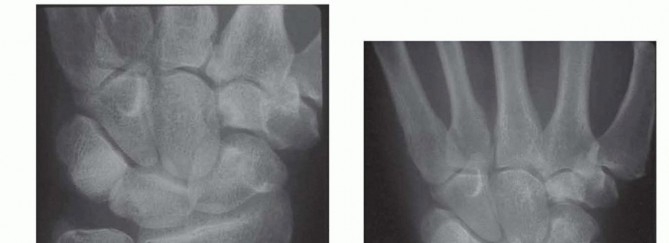

FIG 3 • A. Ulnar-plus variance unequivocally demonstrated on a standardized 90/90 neutral rotation PA view, confirming the mechanical basis for the patient's abutment syndrome.

On this view, we carefully scrutinize the proximal ulnar pole of the lunate and the radial aspect of the triquetrum for subchondral sclerosis or cystic changes, which are pathognomonic for chronic impaction. We then template the exact amount of ulnar shortening required. Our surgical objective is to achieve a final ulnar variance of minus 1 to minus 2 mm.